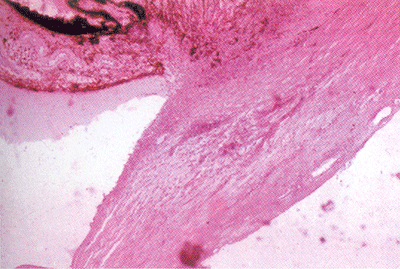

浆液性虹膜炎基础图谱

浆液性虹膜炎